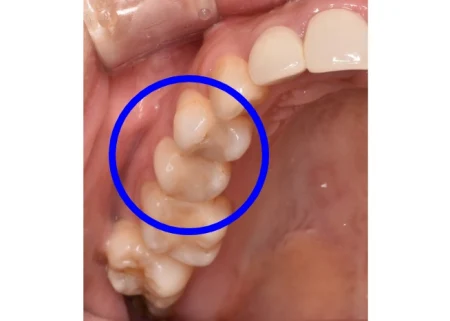

セラミック 2023.0240代女性「保険の銀歯を白くしたい」目立っていた金属の詰め物を外し、透明感と強度のあるセラミック「E-maxアンレー」で見た目も美しく修復した症例